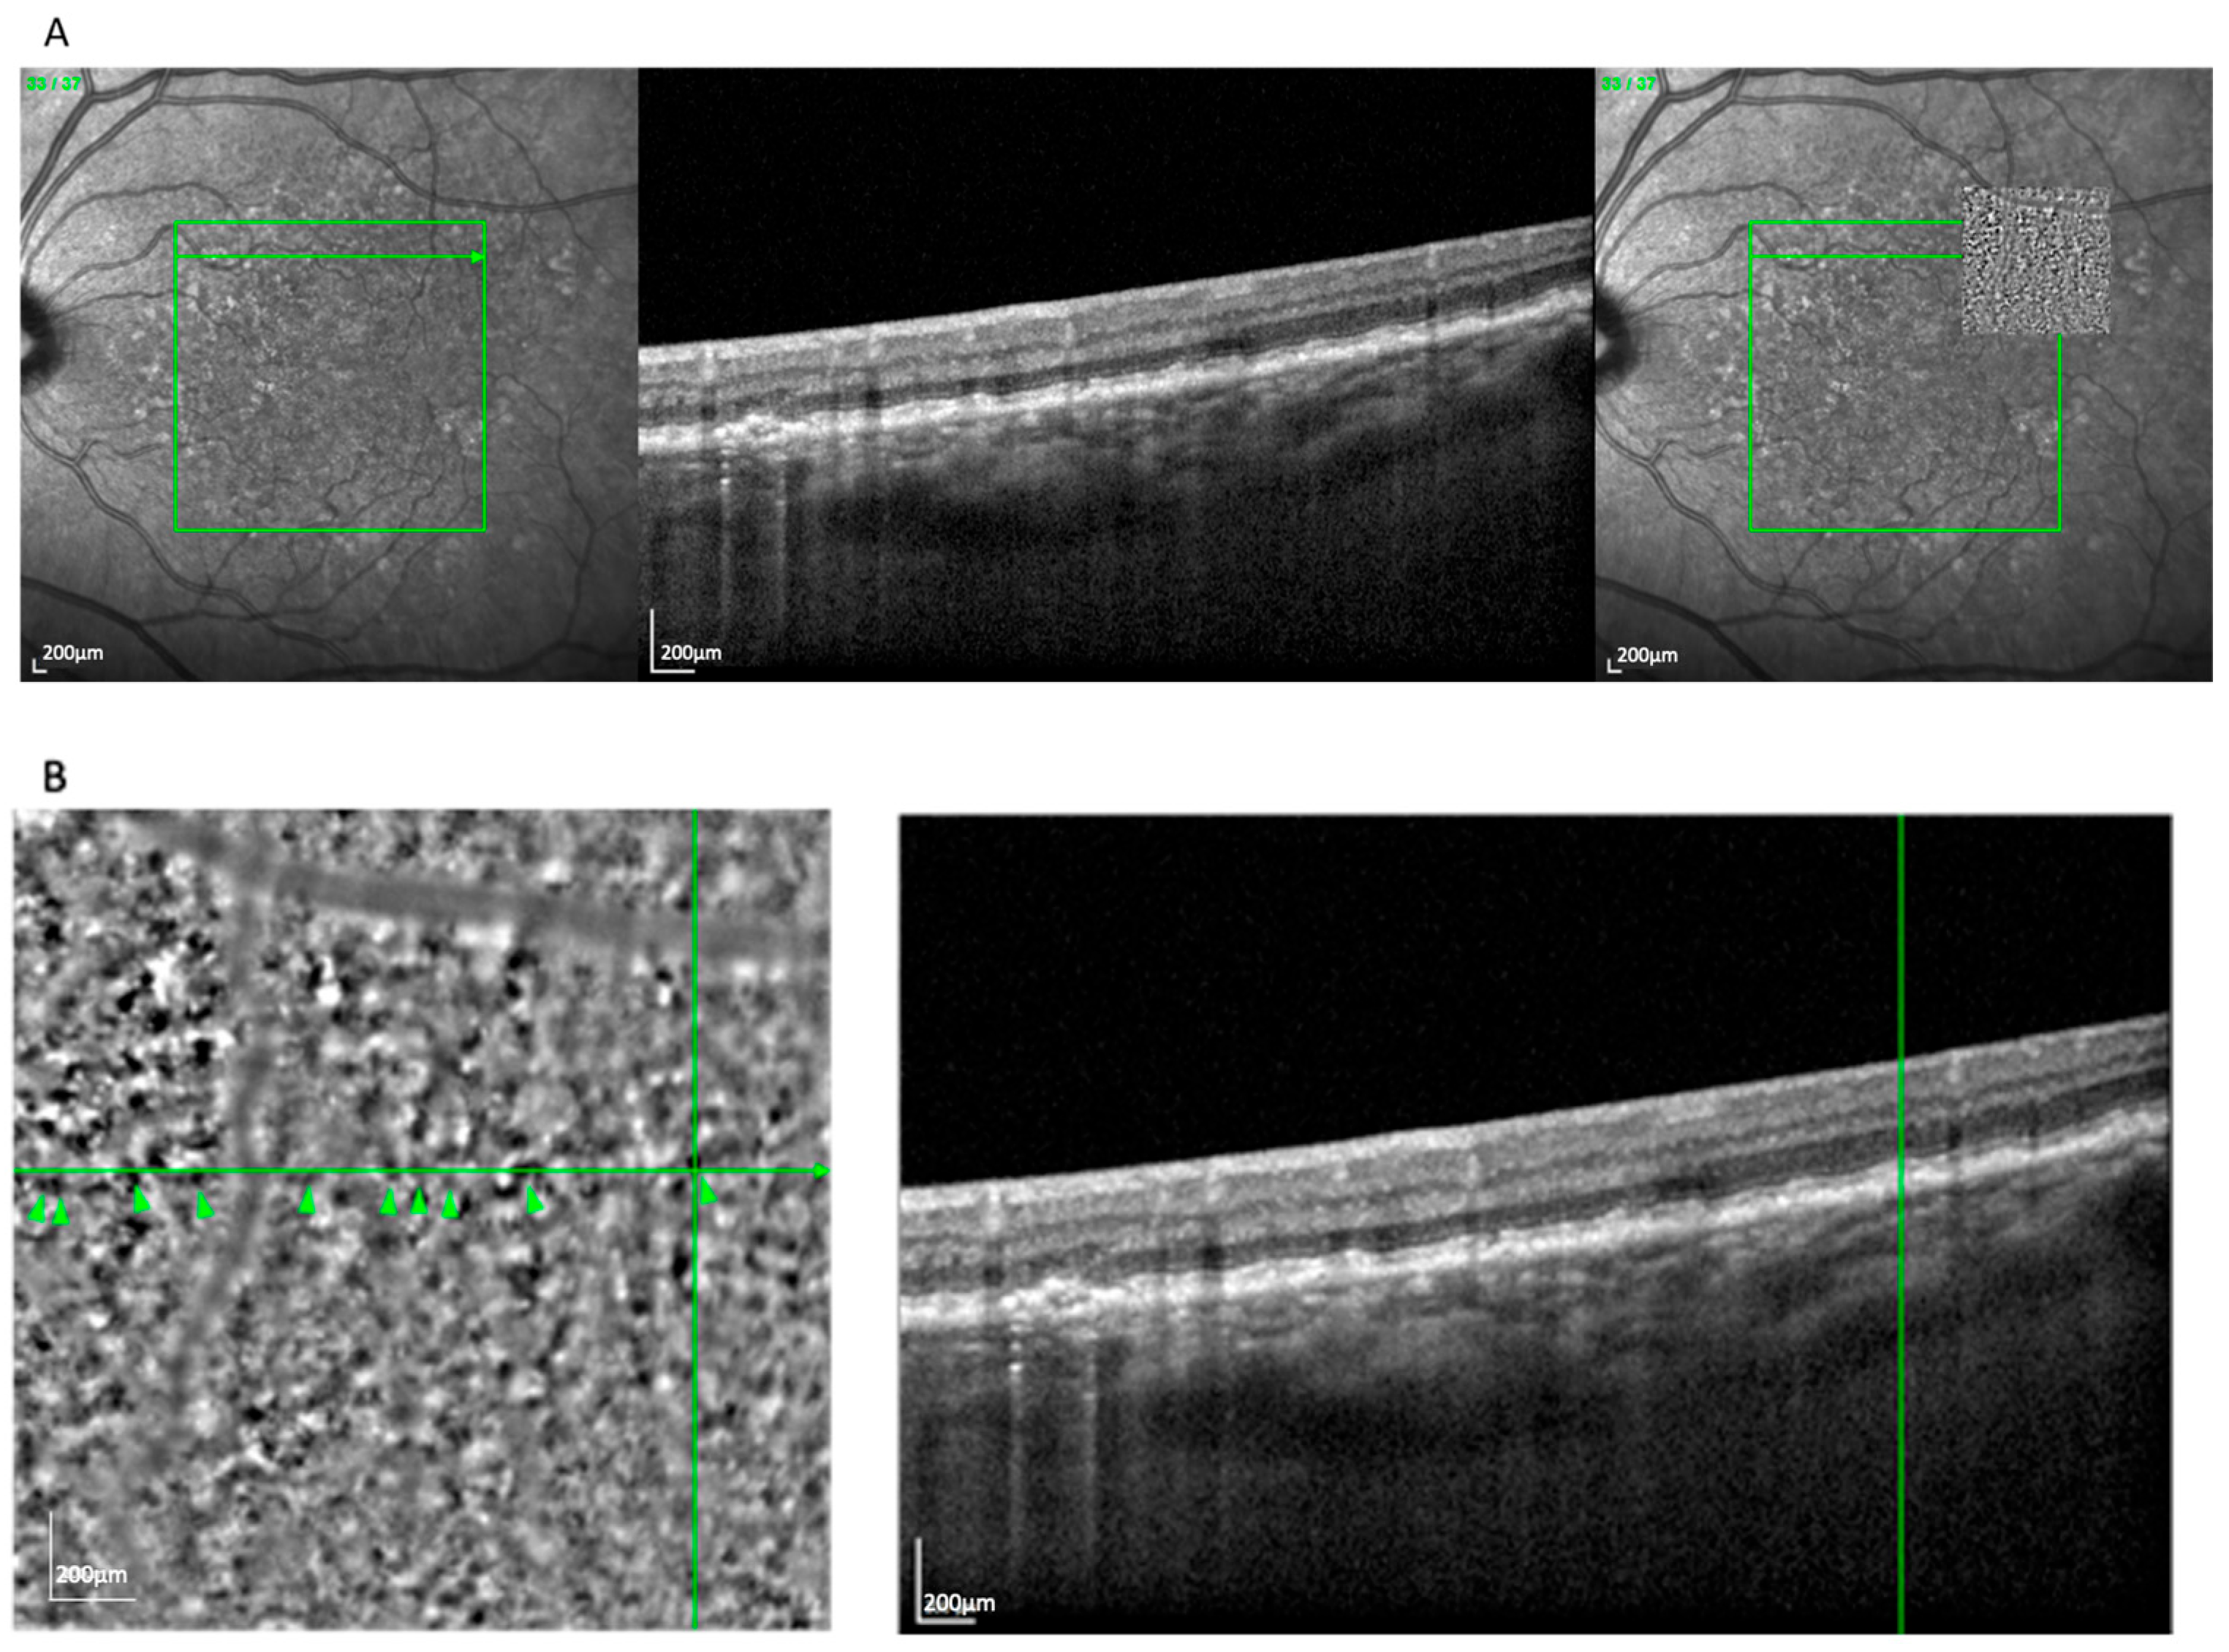

The drop pattern (Figure 4), observed in 14 eyes (11.6%), presented as several well-separated, homogeneously sized hyporeflective zones, often located above the RPE layer and surrounded by hyperreflective rims. This appearance aligned with reticular pseudodrusen, particularly stage 3 morphology, as seen on OCT [18]. The localization and structural profile further supported this classification. This pattern was more frequently seen in GA (71.4%) than in nvAMD (28.6%).

Figure 4.

(A) Correlation of drop lesions visible on an AO-TFI image in RPE mode with the OCT finding using vessel structure for orientation. (B) Visualization of drops and high-magnification view of the correlated reticular pseudodrusen. Green lines highlight corresponding on between en face and cross-sectional view. Arrowheads show the Pattern Drops.